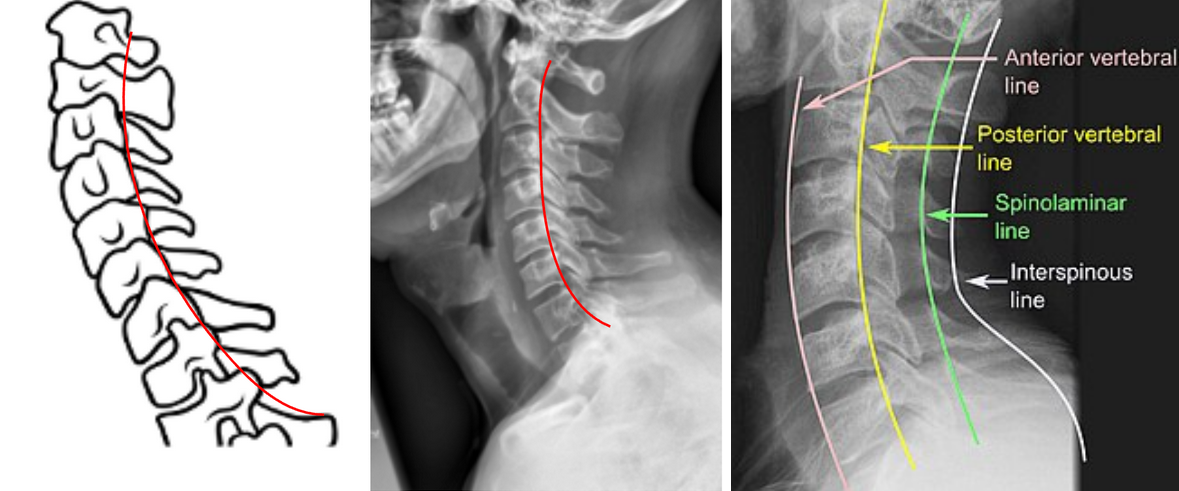

George’s Line (Posterior Cervical Line)

George’s Line, also known as the Posterior Cervical Line, is a radiographic alignment assessment tool used to evaluate sagittal continuity of the cervical vertebral column.

It is drawn along the posterior vertebral body margins on a lateral cervical spine X-ray, and should form a smooth, continuous curve from C2 through C7.

Disruption or step-off of this line suggests subluxation, dislocation, fracture, or instability—most often due to trauma, degenerative spondylolisthesis, or ligamentous injury.

Should be assessed in conjunction with posterior spinolaminar line and anterior vertebral body line for a complete evaluation of sagittal integrity.